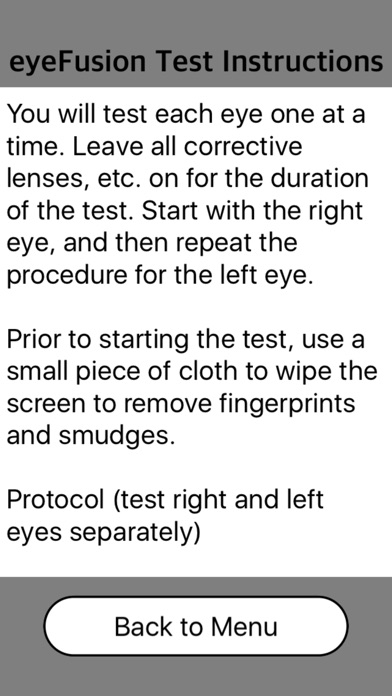

eyeFusion is an application to measure your flicker fusion threshold (also referred to as visual conductance or flicker sensitivity) through self-testing.